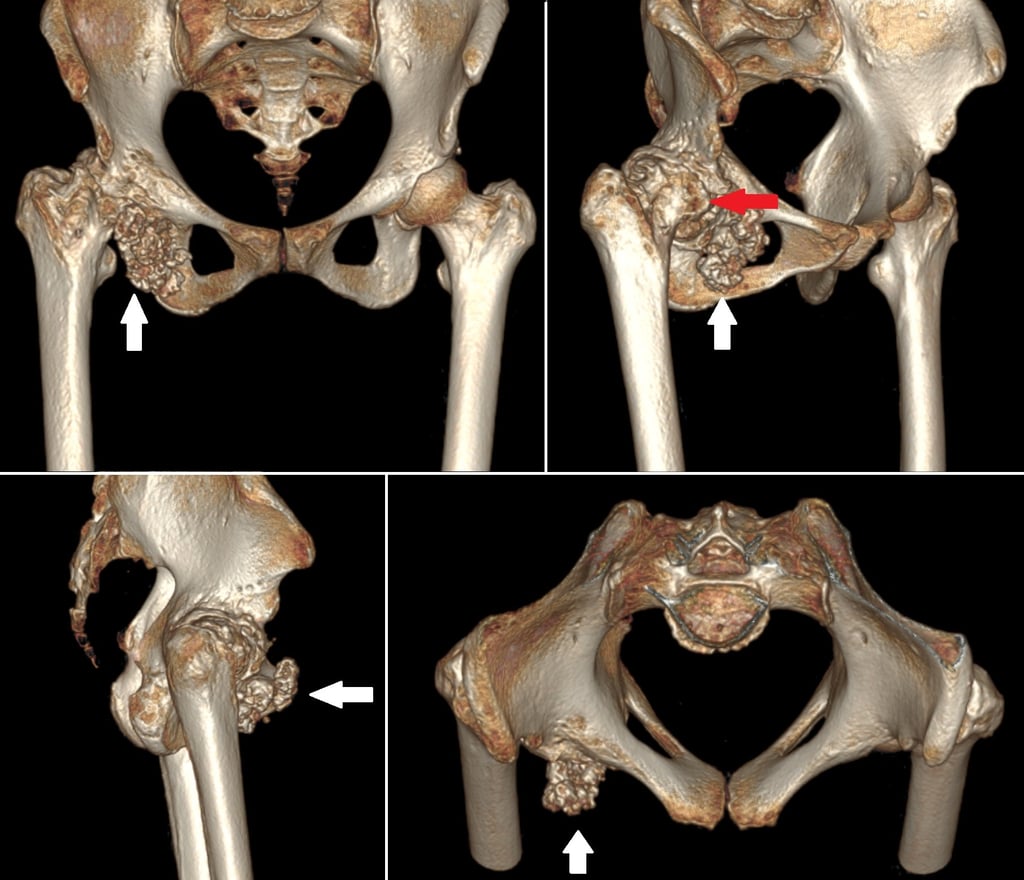

Giant synovial chondromatosis of hip

Synovial chondromatosis is a rare, benign condition occurring due to metaplasia of synovium leading to cartilaginous nodules, which may mineralise, break free to form loose bodies or even ossify. The aetiology still remains unknown. It usually involves the knee joint, and very rarely involves the hip. It usually occurs in the third to fifth decades of life and is more common in males. The clinical presentation is usually of pain, swelling and restriction of movements of the joint involved. Radiographs, CT and MRI can diagnose the condition in most cases. We discuss a case of giant synovial chondromatosis of the hip presenting with secondary osteoarthritis of the hip joint.